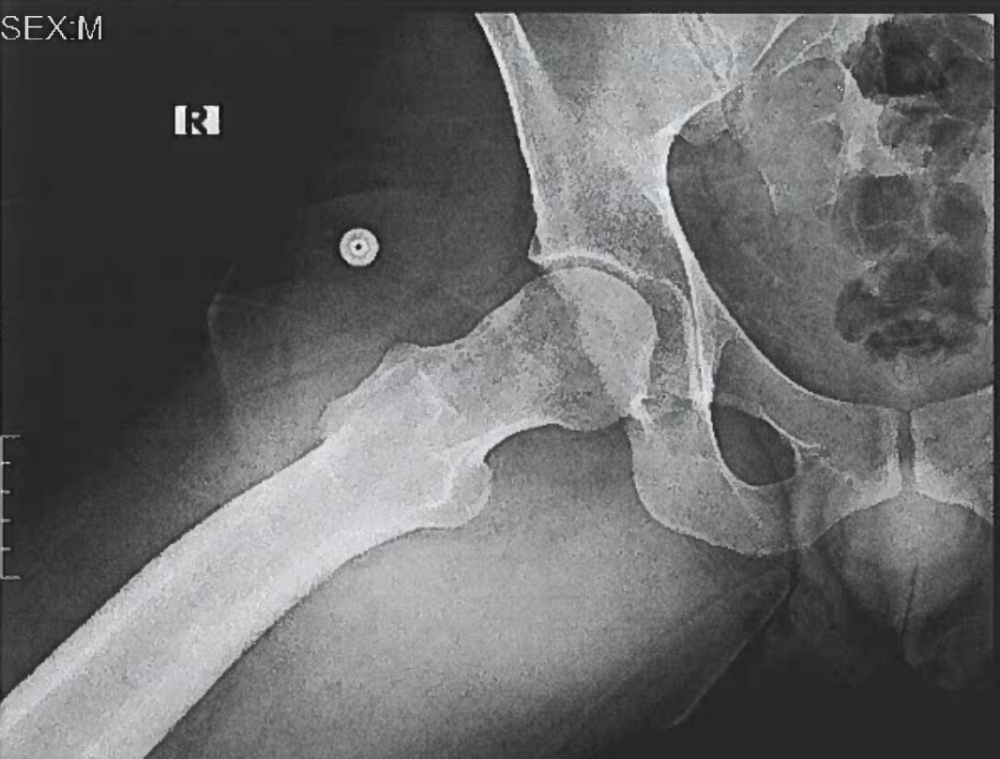

avgjoe913 Posted June 17, 2025 Report Posted June 17, 2025 (edited) Fun fact: dicks are visible on X-Rays! I recently had an X-Ray done of my hip, and after the appointment was over, I remembered that I'd previously seen something about dicks showing up on X-Rays (it was a thing that happened with the tennis player Andy Murray, you can look it up). The doctor did go over the X-Ray with me during the appointment, but we were obviously focused on my hip (which is fine), so I was very curious to see if I'd notice anything when looking at it on my own in the Patient Portal. I thought maybe only bigger ones are visible, and at first that seemed to be the case - I couldn't see anything. But it's sort of like those Magic Eye pictures - once you look at it for a little while and your eyes and brain figure out what they should be looking for, you see it. And it's certainly there - a shadowy but surprisingly accurate image of my penis, the top part of my scrotum, and my thigh next to them. Like many of you guys, it's basically just a head when I'm totally soft, and that was obviously the case in this situation, so it sort of just looks like part of my pubic bone at first glance. Alas. If you look up other examples, bigger ones are much easier to see. It's kind of funny to look at. I'm surprised this is not more well-known, to be honest. Anyway, I'm not sure if I can post it here, so for now, PM me if you're interested in seeing it. If I get the OK from the mods, I'll post it. Edited June 17, 2025 by avgjoe913 Grimson, LilGonzalote, Grizz10231 and 2 others 5

avgjoe913 Posted June 21, 2025 Author Report Posted June 21, 2025 Ha, well then I guess I'll go ahead and post mine! It looks like the contrast or something is different on yours, not sure why that is. Seems like there's less detail, but can still easily see what you're packing, lol. Grizz10231, A-RB, grandstand and 3 others 5 1